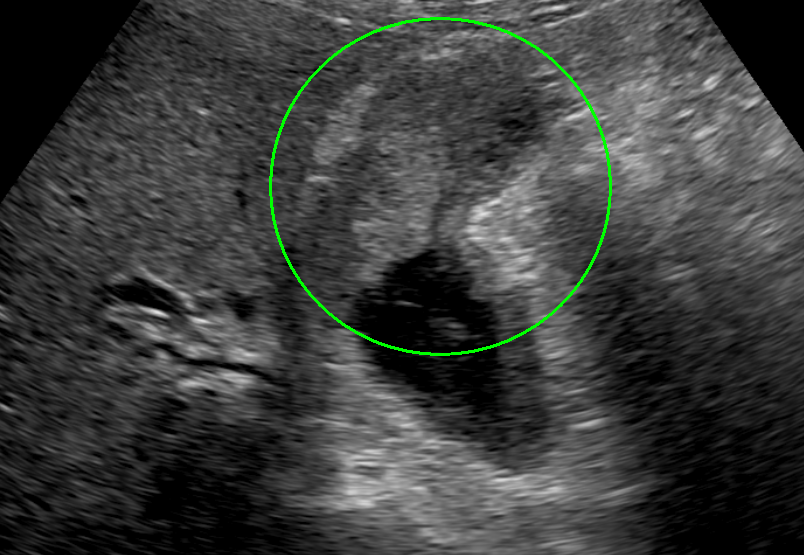

超音波内視鏡(EUS)画像